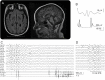

Pathogenic variants in the SACS gene (OMIM #604490) cause autosomal recessive spastic ataxia of Charlevoix-Saguenay (ARSACS). ARSACS is a neurodegenerative early-onset progressive disorder, originally described in French Canadians, but later observed elsewhere.(1) Whole-exome sequencing of a large group of patients with unclassified progressive myoclonus epilepsies (PMEs) identified 2 patients bearing SACS gene mutations.(2) We detail the PME clinical features associated with SACS mutations and suggest the inclusion of the SACS gene in diagnostic screening of PMEs.